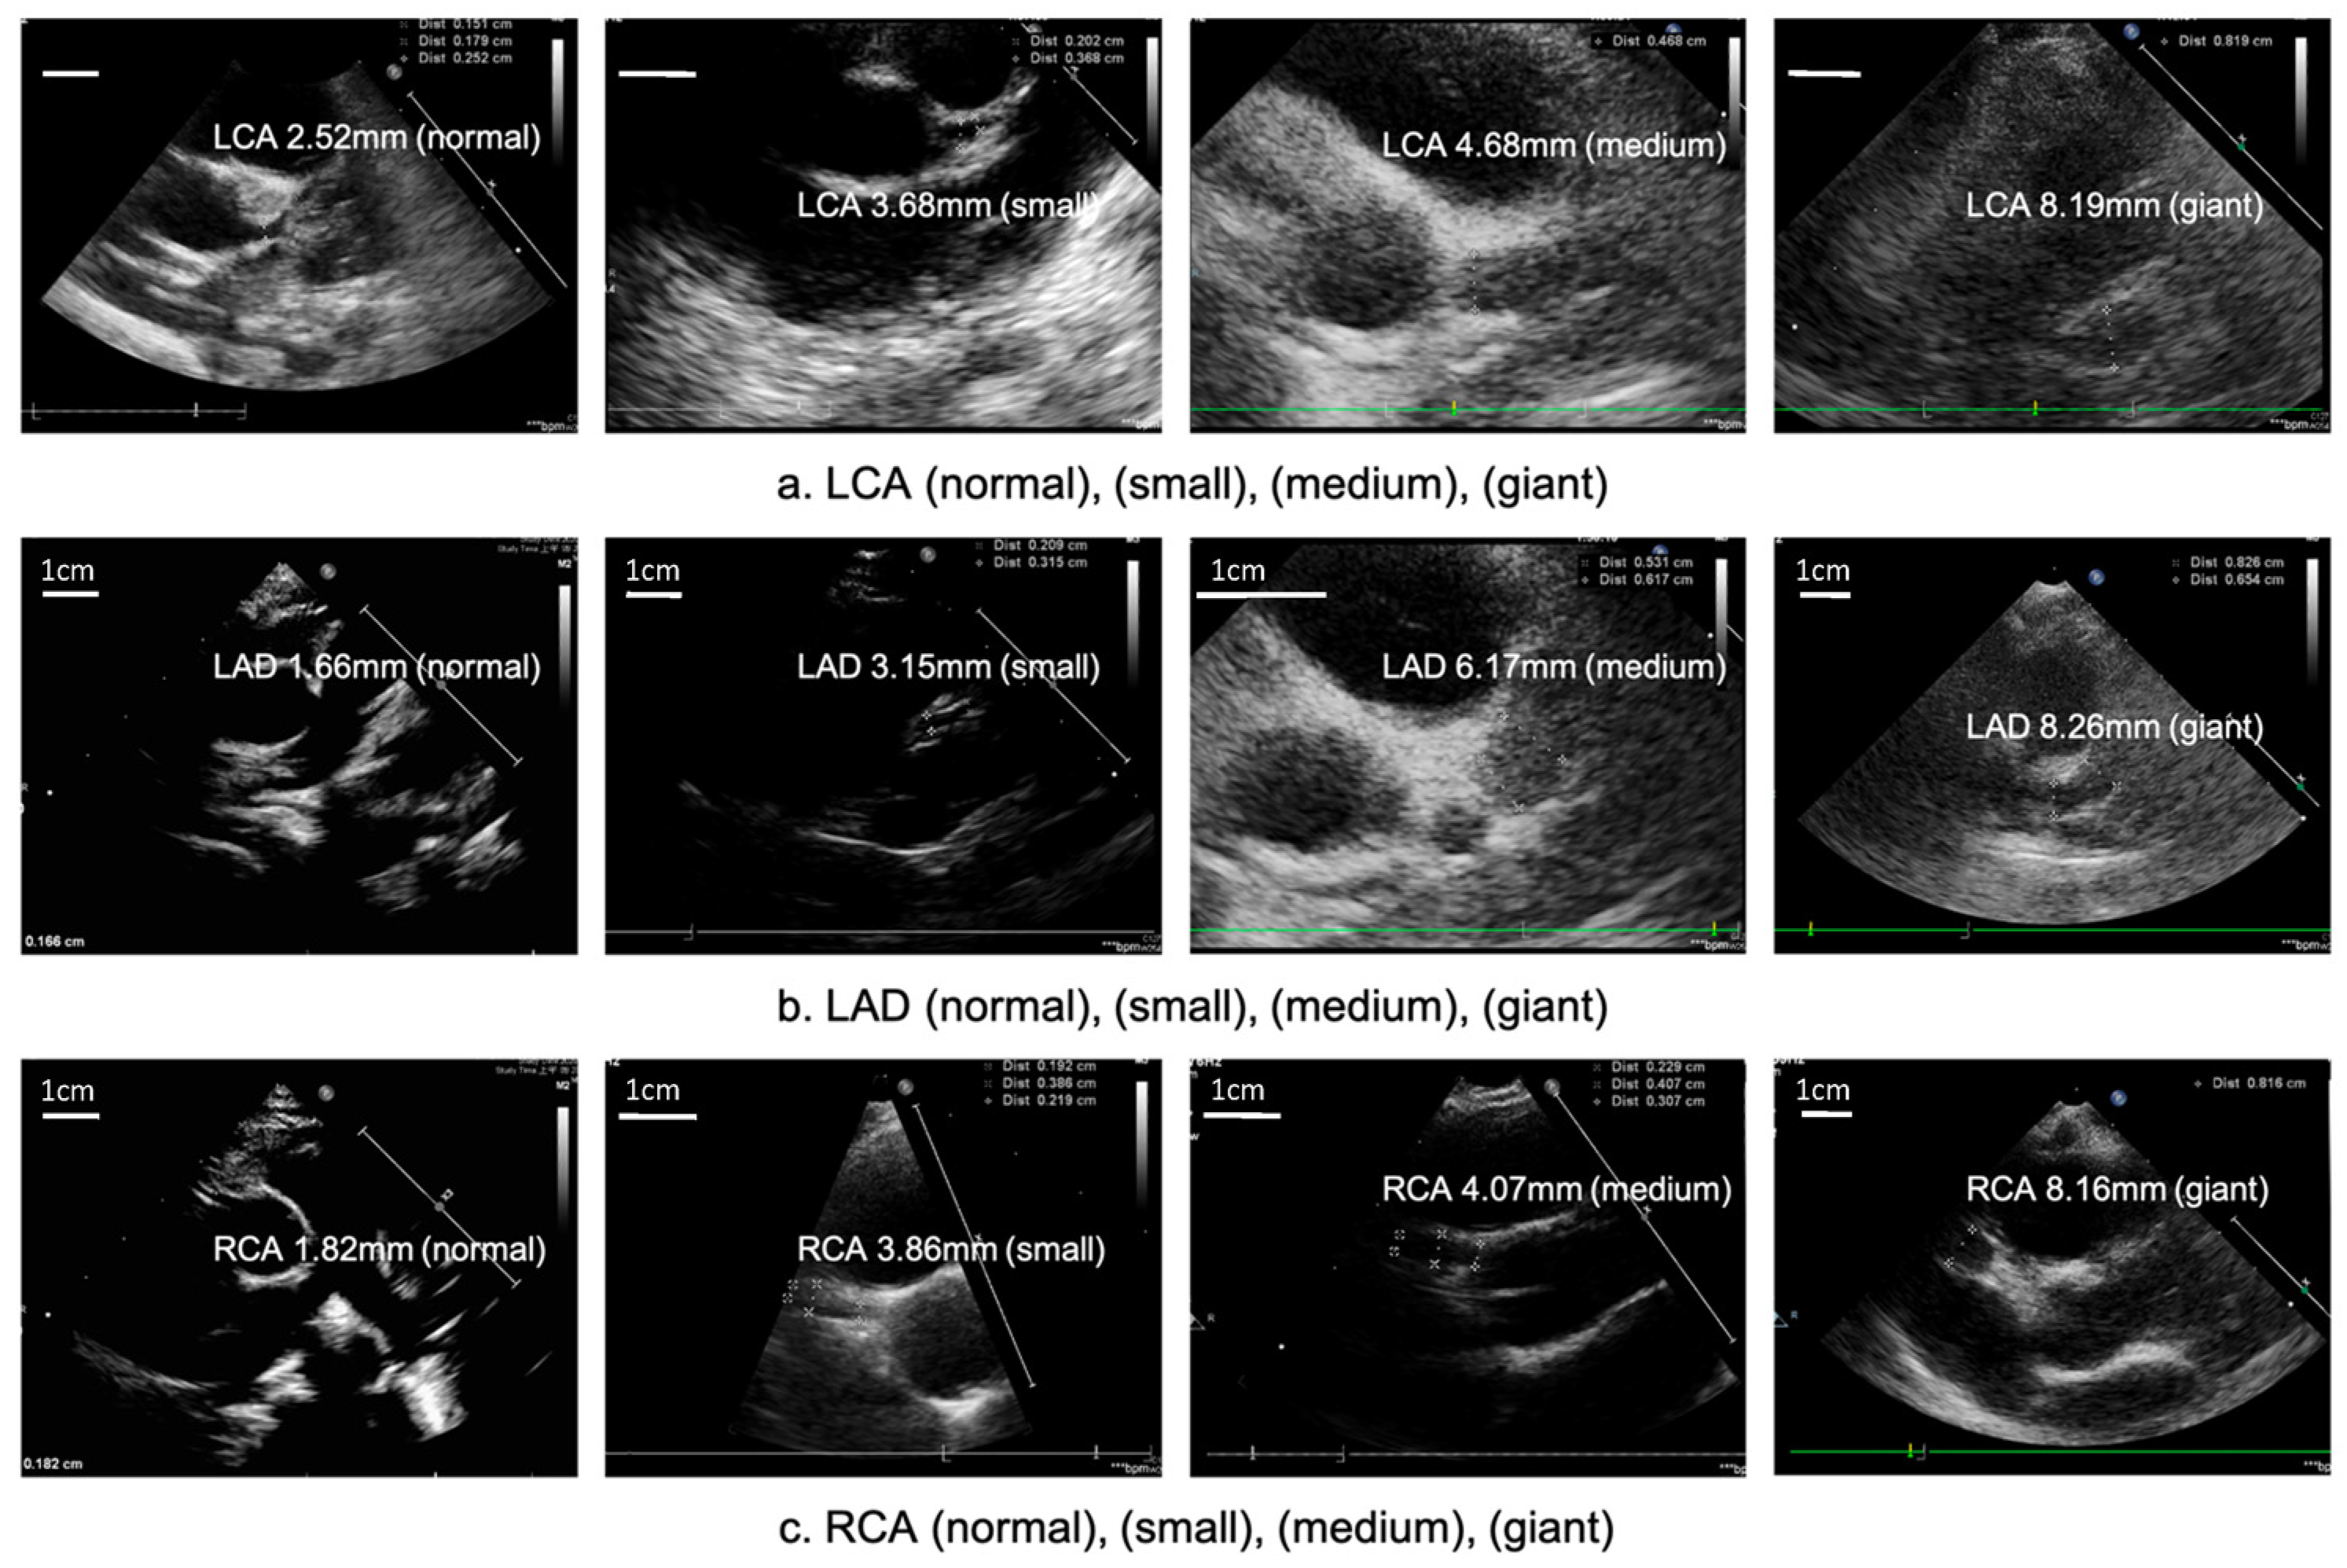

| American Heart Association (AHA) Guidelines: [2] | Japan Circulation Society Guideline: Classification of Coronary Aneurysms during the Acute Phase |

| Positive findings for KD Include: 1. Left anterior descending coronary artery or right coronary artery with a Z-score ≥ 2.5 2. Coronary artery aneurysm formation 3. ≥3 of the following suggestive features: mitral regurgitation, pericardial effusion, decreased left ventricular function, or Z-scores in the left anterior descending coronary artery or right coronary artery of 2 to 2.5. Z-score classification of coronary artery lesions by AHA: 1. Dilatation only: Z-score 2 to 2.5 2. Small aneurysm: Z-score ≥ 2.5 to 5 3. Medium aneurysm: Z-score ≥ 5 to 10 or absolute measurement <8 mm 4. Large aneurysm: Z-score ≥ 10 or absolute measurement ≥8 mm | 1. Small aneurysms or dilatation: Children < 5 years old: localized dilatation of coronary artery >3 mm but within ≤4 mm internal diameter Children ≥ 5 years old: localized dilatation of coronary artery >4 mm or if the internal diameter of a segment measures <1.5 times that of an adjacent segment 2. Medium aneurysms: Children < 5 years of age: an internal diameter of the coronary artery from >4 mm to <8 mm Children ≥ 5 years of age: the internal diameter of a coronary artery segment measures 1.5–4 times that of an adjacent segment 3. Giant aneurysms: Children < 5 years of age: coronary artery with an internal diameter of ≥8 mm Children ≥ 5 years of age: the internal diameter of a coronary artery segment measures >4 times that of an adjacent segment |